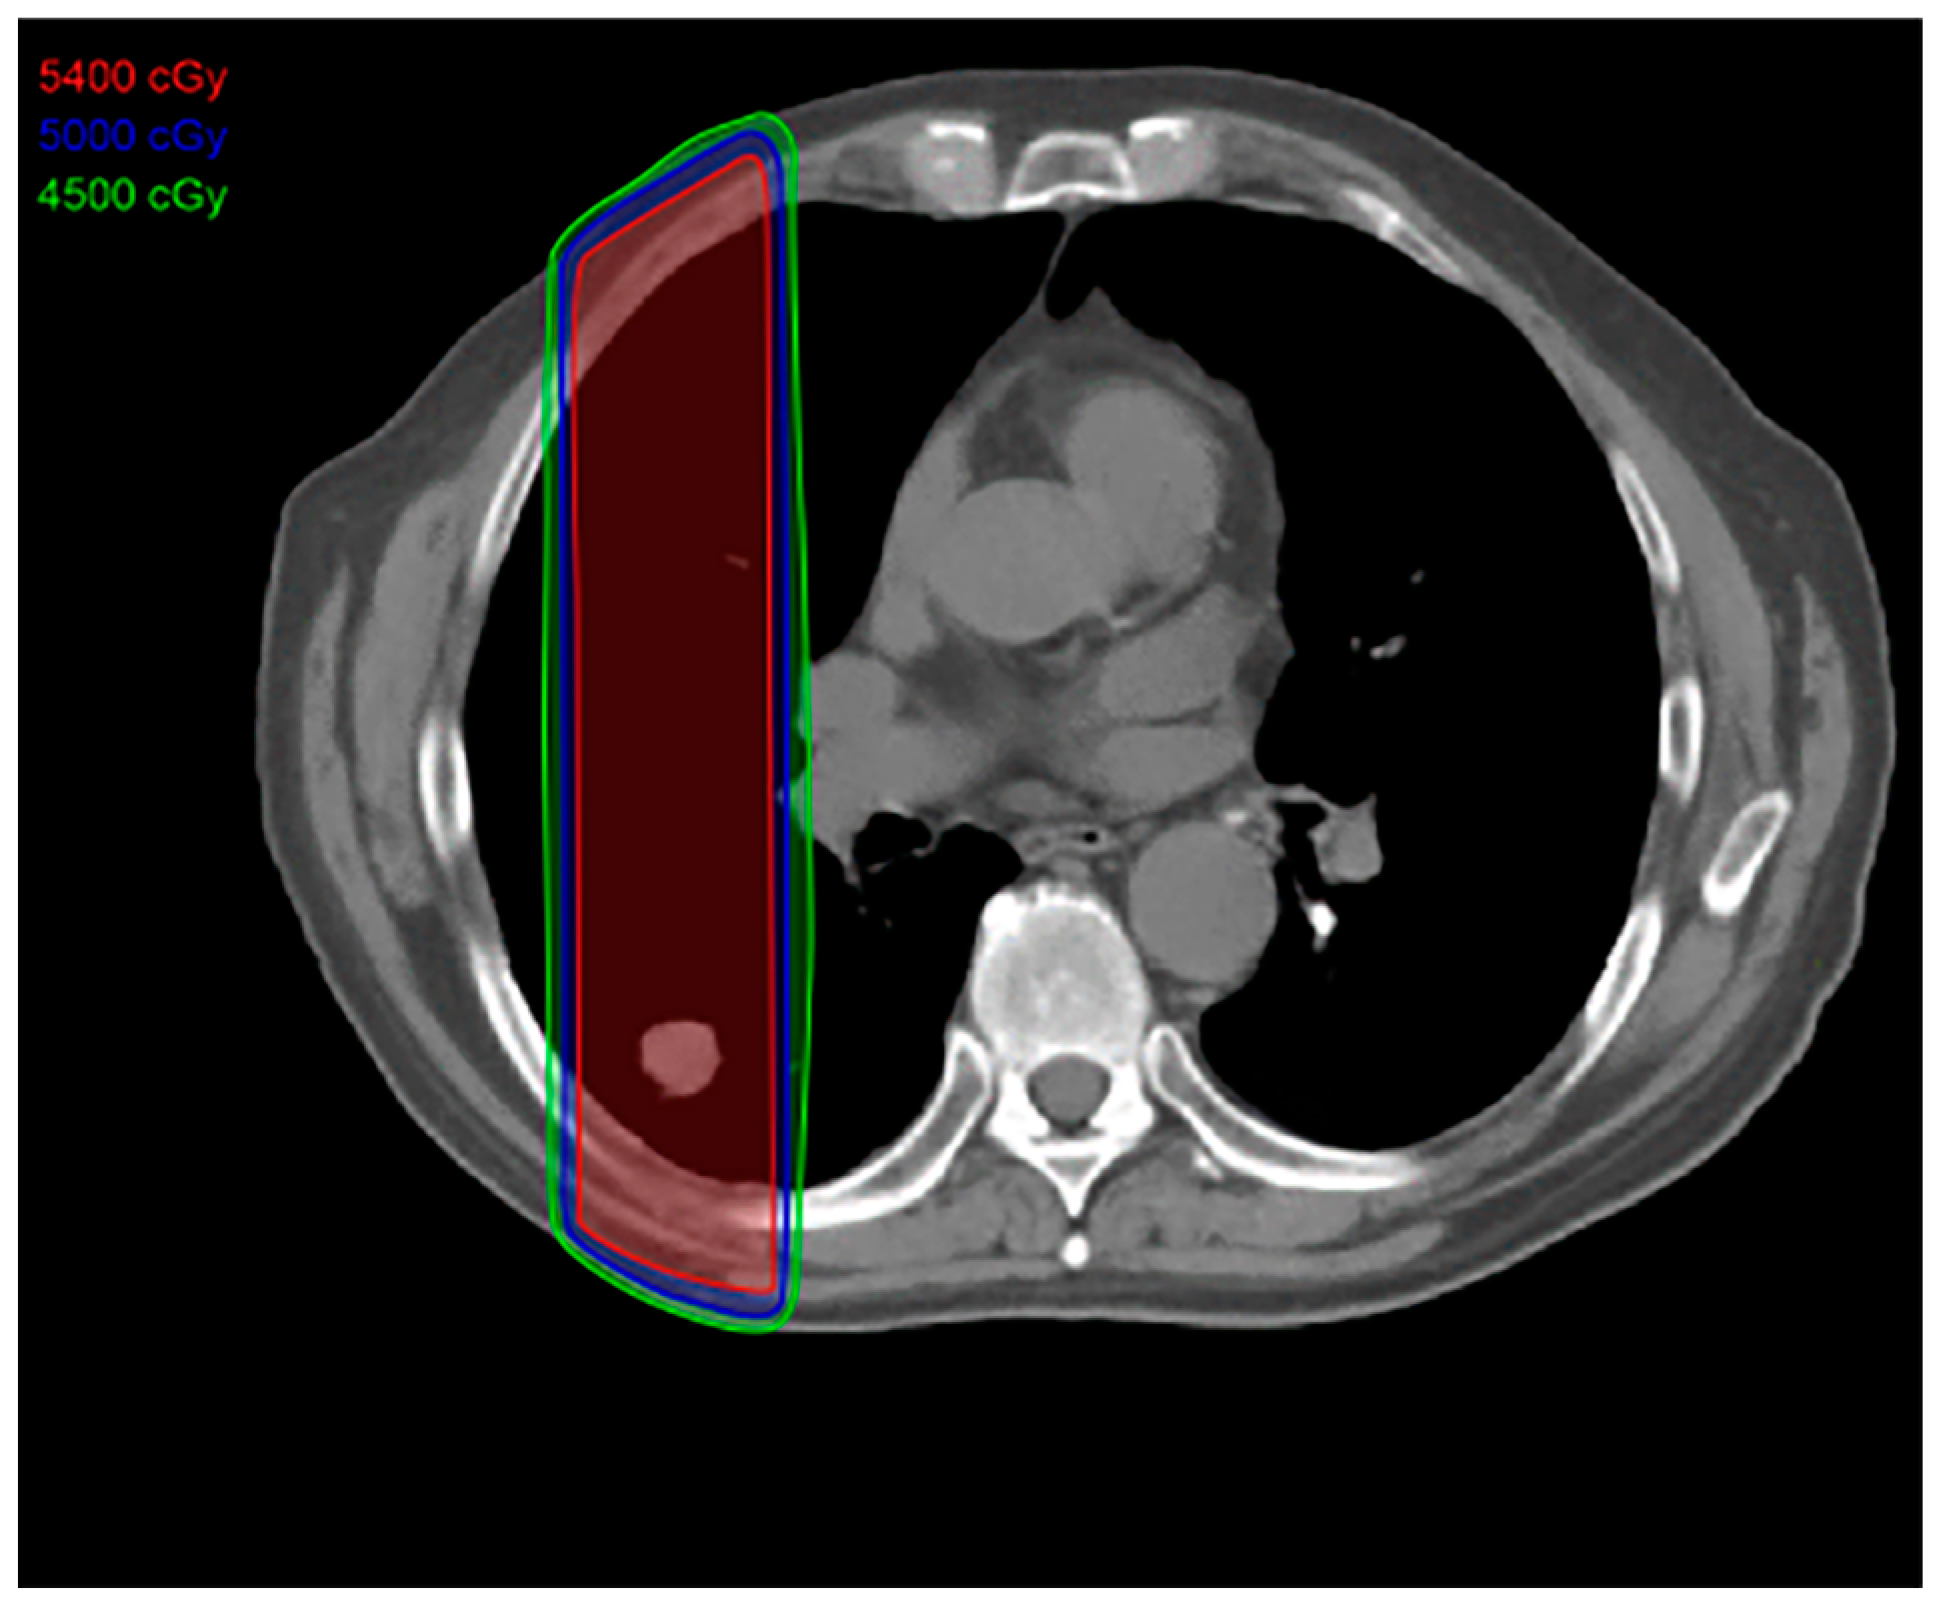

2.2. Three-Dimensional Conformal Radiotherapy